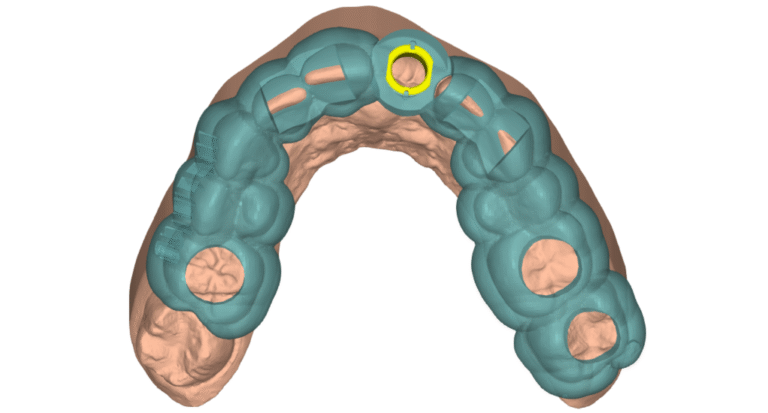

Gingiva Contouring Guide

These guides are used to contour the gingiva in healed sites to ensure a more aesthetic emergence profile.

These guides are designed from the design of the final restoration. A soft tissue laser is typically used.